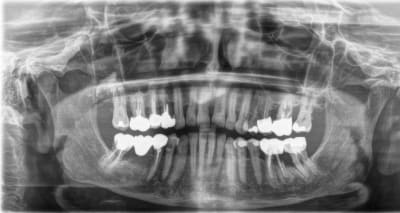

Patiente 97 ans. en pleine forme. Pas de problèmes ressenties au niveau buccale.

Que faites-vous de la 36 ?

Abcès en apical de 36, dent qui va casser à terme et suspicion en distal de la 35. Extrait tant que ca fait pas mal en fonction de l’état de santé.

Les deux traitements endos sont très différents et la couronne sur 37 ressemble à une couronne bague plus ancienne à la radio.

35, 36, 37, 26, 27 ça merde à tous les étages: soit on reprend tout (paro/occluso ici ça craint), soit on pallie à la symptomatologie au fur et à mesure et au plus simple: d'abord carie 35, puis si symptomatique avulsion 36 (pas de bricolage avec récupération de racine), puis on gère au fur et à mesure des symptômes.

Je signale que 36 est perdue à terme. Avec la possibilité d'exo de suite.

J'explique qu'il y aura extraction si complications au niveau de la dent, MAIS AUSSI ET SURTOUT en cas de pathologies générales.

Je n'ai pas vu la question de PPère (je ne la vois toujours pas !) Non pas solidarisées

35 grosse mylolyse donc Flow fait.

J'ai dégagé la gencive en périphérie de la racine D de 36 et j'ai mis un Fuji type rustine pour surtout pour accéder à la racine lors de la casse probable ultérieure. Voila ! J'ai fait comme cela, mais dans le doute quand même (comme avec à peu près tous mes patients).

Admiration pour ta patiente qui a tres bien entrenu ses dents et aux prats qui ont fait du bon boulot.

Jeter de temps en temps un coup d'oeil bienveillant a sa 36 et avertir tan patiente .

Par contre contrairement a vulpi, si la 36 lache ou fait un petit abces chronique interradiculaire , je serais pour (esssayer) extraction racine distale couronnes racine mesiale 36 et 37 solidarisées. Rester simple, a l'ancienne :-))))